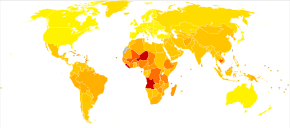

no data

< 10

10-14

14-18

18-22

22-26

26-30

|

30-34

34-38

38-42

42-46

46-50

> 50

|

Complications of acute otitis media consists of perforation of the ear drum, infection of the mastoid space behind the ear (mastoiditis), and more rarely intracranial complications can occur, such as bacterial meningitis, brain abscess, or dural sinus thrombosis.[46] It is estimated that each year 21,000 people die due to complications of otitis media.[47]

Acute otitis media is very common in childhood. It is the most common condition for which medical care is provided in children under five years of age in the US.[14] Acute otitis media affects 11% of people each year (709 million cases) with half occurring in those below five years.[47] Chronic suppurative otitis media affects about 5% or 31 million of these cases with 22.6% of cases occurring annually under the age of five years.[47] Otitis media resulted in 2,400 deaths in 2013 — down from 4,900 deaths in 1990.[11]